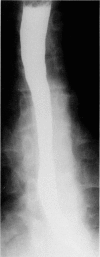

Diffuse intramural pseudodiverticulosis of the esophagus is a rare cause of dysphagia. A 19-year-old patient with a long history of recurrent episodes of food impaction was diagnosed with diffuse intramural pseudodiverticulosis. The clue to diagnosis is a critical and thorough review of the barium swallow. Treatment is aimed toward dilatation of strictures and treatment of inflammation.